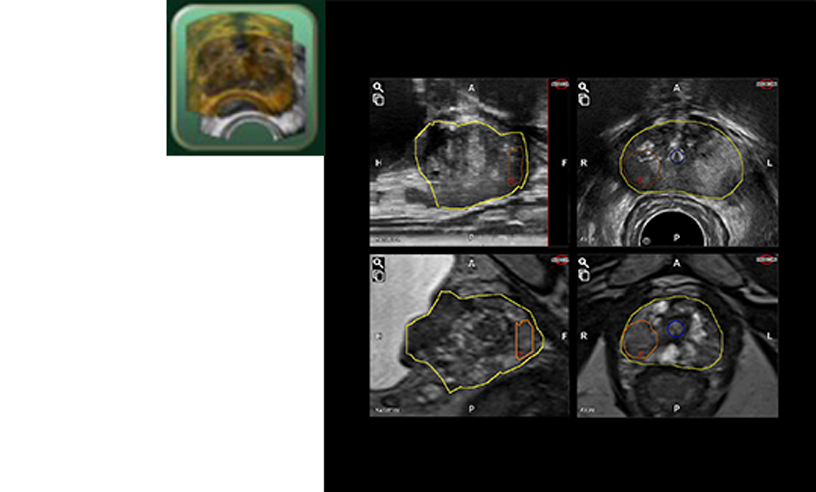

- Available Rigid and Elastic fusion

- Fine adjustment of the contour for each Axial, Sagittal, and Coronal plane.

- Fusion DWI/ADC*2 and T2W*3 images with Ultrasound 3D volume.